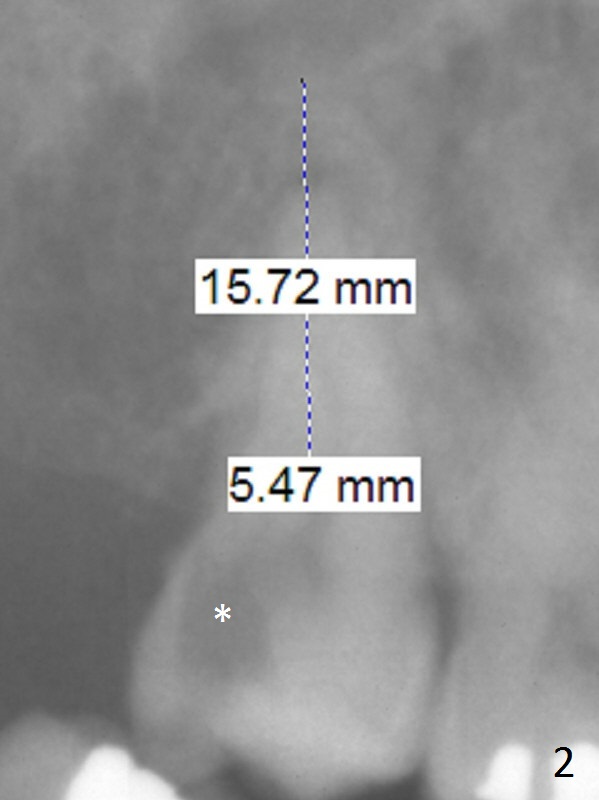

A 51-year-old woman requests extraction of the upper right 2nd molar (Fig.1) with caries and sensitivity (Fig.2 *). After discussion of treatment options including RCT, she chooses implant. The tooth has most likely fused roots and single socket. Try to use tap drills to form osteotomy palatal and deep.